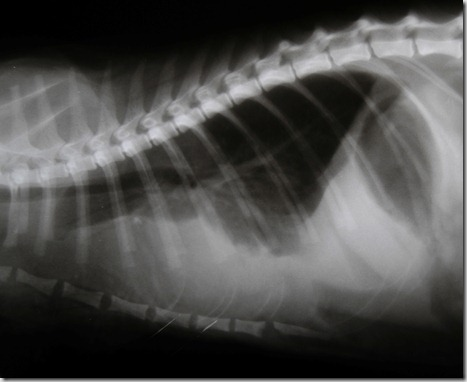

Radiografia

L’esame radiografico è uno step fondamentale nell’indagine diagnostica di base. La clinica è dotata di un apparecchio radiografico digitale diretto ad alta risoluzione che consente di ottenere immagini dettagliate e visualizzate istantaneamente, riducendo così il tempo di esecuzione dell’esame e risparmiando stress al paziente. Le immagini vengono archiviate nel nostro database e possono essere trasmesse per via telematica.